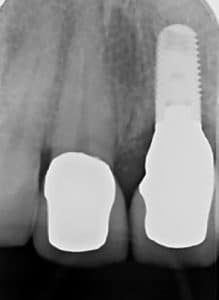

To qualify for dental implants, you must have enough bone in your jaw. When you lose a tooth, the bone that helped hold that tooth in place will naturally deteriorate. In fact, most bone loss happens during the first six months after tooth loss [1]. The longer you wait to replace the tooth, the more the bone will deteriorate.

Bone preservation is when Dr. Marlin reintroduces a small amount of bone into the empty socket after a tooth extraction before sealing the wound. This process helps preserve the socket and the bone quality for future restorations [2]. With bone preservation, it’s much easier to place a dental implant once the area heals.

Dental implants with our practice have an impressive success rate of over 97%, lasting a minimum of 20 years for patients at Elite Prosthetic Dentistry, even though the national average for dental implant restoration success over the same time period is only 83.4% [3]. However, in order for dental implants to be properly placed and last for decades with proper care, you need to have enough bone in your jaw [4].

Since dental implants allow you to bite, chew, and essentially have all the functions of a natural tooth, they must be secure in your jaw. To correctly place a dental implant for successful healing and fusion with your natural jawbone, enough bone with good density must initially exist in the area.